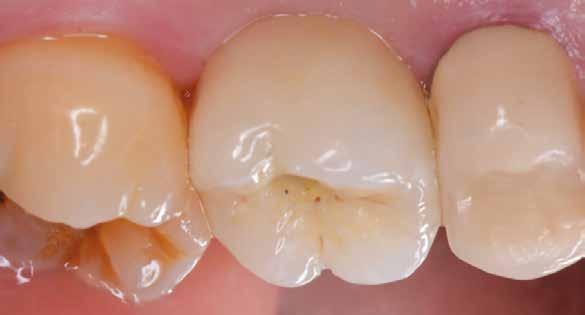

Protetikai eljárás

A teljesen digitalizált protetikai munkafolyamat során az Exocad szoftver segítségével (exocad) egy hibrid, csavarrögzített, cirkónium monolit koronát gyártottunk le copaSKY

uni.fit titánalapra (bredent medical). Az implantátum körül a bukkális lágyszövet megfelelő vastagságot és kedvező ínykontúrt mutatott (12. a–b. ábra). Az egyedi ínyformázó eltávolítása után egészséges implantátum körüli lágyrészgallér

értünk el (19. ábra). Az okkluzális nyílást tefloncsíkkal és kompozittal zártuk (20. ábra). Mindezek után, posztoperatív kontroll röntgenfelvétel készült, amely a pótlás megfelelő illeszkedését mutatta (21. ábra). A hat hónapos utánkövetés során jól megfigyelhető a teltebb lágyszöveti profil és a megtartott kresztális csontszint (22–24. ábra)

volt megfigyelhető (13–14. ábra), ezen kívül közvetlenül a műtét előtt intraorális vizsgálatot végeztünk a lágyszöveti profil megállapítása érdekében. Ezt követte a scanbody behelyezése, így digitális lenyomat készült az implantátum pozíciójáról (15. ábra). Ugyanezzel a technikával rögzítettük az antagonista fogívet és a harapást is. Az így kapott STL-fájlokat digitálisan továbbítottuk a fogtechnikai laboratóriumba. A titánalapra PMMA ideiglenes koronát készítettünk a proximális és marginális illeszkedés ellenőrzése érdekében, valamint a megfelelő harapás elérése céljából (16–17. ábra) Miután az összes igazítás elkészült, ismételt vizsgálatot végeztünk. A végleges hibrid csavarrögzítésű, teljes kontúrú cirkóniumkoronát titánalapon erősen polírozott szubgingivális résszel készítettük el, és 25 Ncm nyomatékra húztuk (18. ábra). Kiváló árnyalategyezést és klinikai eredményt

„tekercslebeny” (roll flap), szubkresztális implantátumbehelyezés a biológiai szélesség megtartása érdekében és az egyedi ínyformázó. Az alkalmazott implantátumrendszert az egyedülálló osseo-connect felület (OCS) miatt választottuk ki, valamint azért, mert az implantátum nyaka támogatja a lágyszöveti zárást, megelőzve a bakteriális beszivárgást, ami védi az implantátumot. A homokfúvott és maratott felület elősegíti a gyors csontosodást. Az implantátum gyökér formájú (tapered), és dupla önvágó kompressziós menettel rendelkezik, amelyek fontosak a magas primer stabilitás eléréséhez. A copaSKY implantátumrendszer platform switchinget alkalmaz a kresztális csontvesztés minimalizálása érdekében, mivel ez kulcsfontosságú az implantátum hosszú távú sikeréhez és stabilitásához. Az önmetsző kettős menet gyorsabb implantátumbehelyezést biztosít alacsonyabb hőtermelés és csontkondenzáció mellett [7]. A homokfúvott és savmaratott, önmetsző menettel ellátott, cilindrikus és egyben gyökér formájú hibrid kialakítású implantátumok statisztikailag nagyobb behelyezési és eltávolítási nyomatékot mutatnak az esztergált implantátumokhoz képest, valamint jobb primer stabilitás érhető el velük [8]. Teljesen digitális protokollt követtünk a végleges pótlás elkészítéséhez. Az intraorális szkennerek olyan eszközök, amelyeket a közvetlen optikai lenyomatok rögzítésére használnak a fogászatban [9]. Az intraorális szkennerek jelenlegi szakirodalmának áttekintése után arra a következtetésre jutottunk, hogy ezek az eszközök időhatékonyak, csökkentik a páciensek kellemetlen fogászati élményeit, kiküszöbölik a gipszmodellek

használatát, és jobb kommunikációt tesznek lehetővé a fogtechnikai laborral [10]. Ebben az esetben egy hibrid csavarrögzített pótlást terveztünk és kiviteleztünk. Egy átfogó áttekintés, amely a csavarozható és ragasztott koronák klinikai jelentőségére összpontosított a döntéshozatalban, azt állapította meg, hogy a csavaros rögzítésű pótlás kevesebb biológiai szövődményt mutat, illetve előnye, hogy könnyen javítható anélkül, hogy károsítaná az ínyformázót és a koronát [11]. A cementtel rögzített korona eltávolítása még mindig nagyobb kihívást jelent és kevésbé kiszámítható, mint egy csavaros pótlásé [11]. Így a csavarozható pótlás leegyszerűsíti a kezelést, amennyiben a jövőben bármilyen komplikáció lépne fel. A cement kifolyása és az implantátum körüli mucosa alatt maradása mikrobiális kolonizációt és az implantátum körüli szövetek károsodását eredményezheti. A csavarrögzített pótlásokkal könnyebben megoldható a szájhigiénia, és egyszerűbben elvégezhetők a fenntartó kezelé-

sek [12]. A végleges pótláshoz polírozott, teljes kontúrú (full contour) cirkóniumkoronát használtunk. A réteges cirkóniumkoronákban a leplezőkerámia hosszan tartó kopás után berepedezést vagy akár leválást mutat, ami a helyreállítás meghibásodását eredményezi [13]. A monolit koronák CAD/ CAM technológiával készülnek, nagy a hajlítószilárdságuk és törésállóságuk, nagyobb, mint az alumínium-oxid alapú kerámiakoronáké [14].

Konklúzió

A precizitásra és tökéletességre való törekvés az implantációs fogászat fejlődéséhez vezetett. A korszerű technikák és anyagok a fogászatban a gyors digitalizációval párosulva javították a páciensek élményét a megnőtt kényelem, a rövidebb kezelési idő és a kiszámíthatóbb eredmények által. A digitális munkafolyamatok minimalizálják a fogorvos, illetve a fogtechnikai labor által esetlegesen okozott manuális és technikai hibákat. Mivel rengeteg implantátumgyártó cég áll rendelkezésre, kulcsfontosságú, hogy olyat válasszunk, amelyik teljesen digitális munkafolyamat lehetőségeket kínál az implantációs fogászatban mind a sebészeti, mind a protetikai szempontok tekintetében. Az implantátum körüli lágy- és keményszövetek jól lefektetett biológiai alapelvei alapján végzett holisztikus kezeléstervezés kiváló esztétikai eredményeket hoz,

hosszú távú sikerhez vezet.